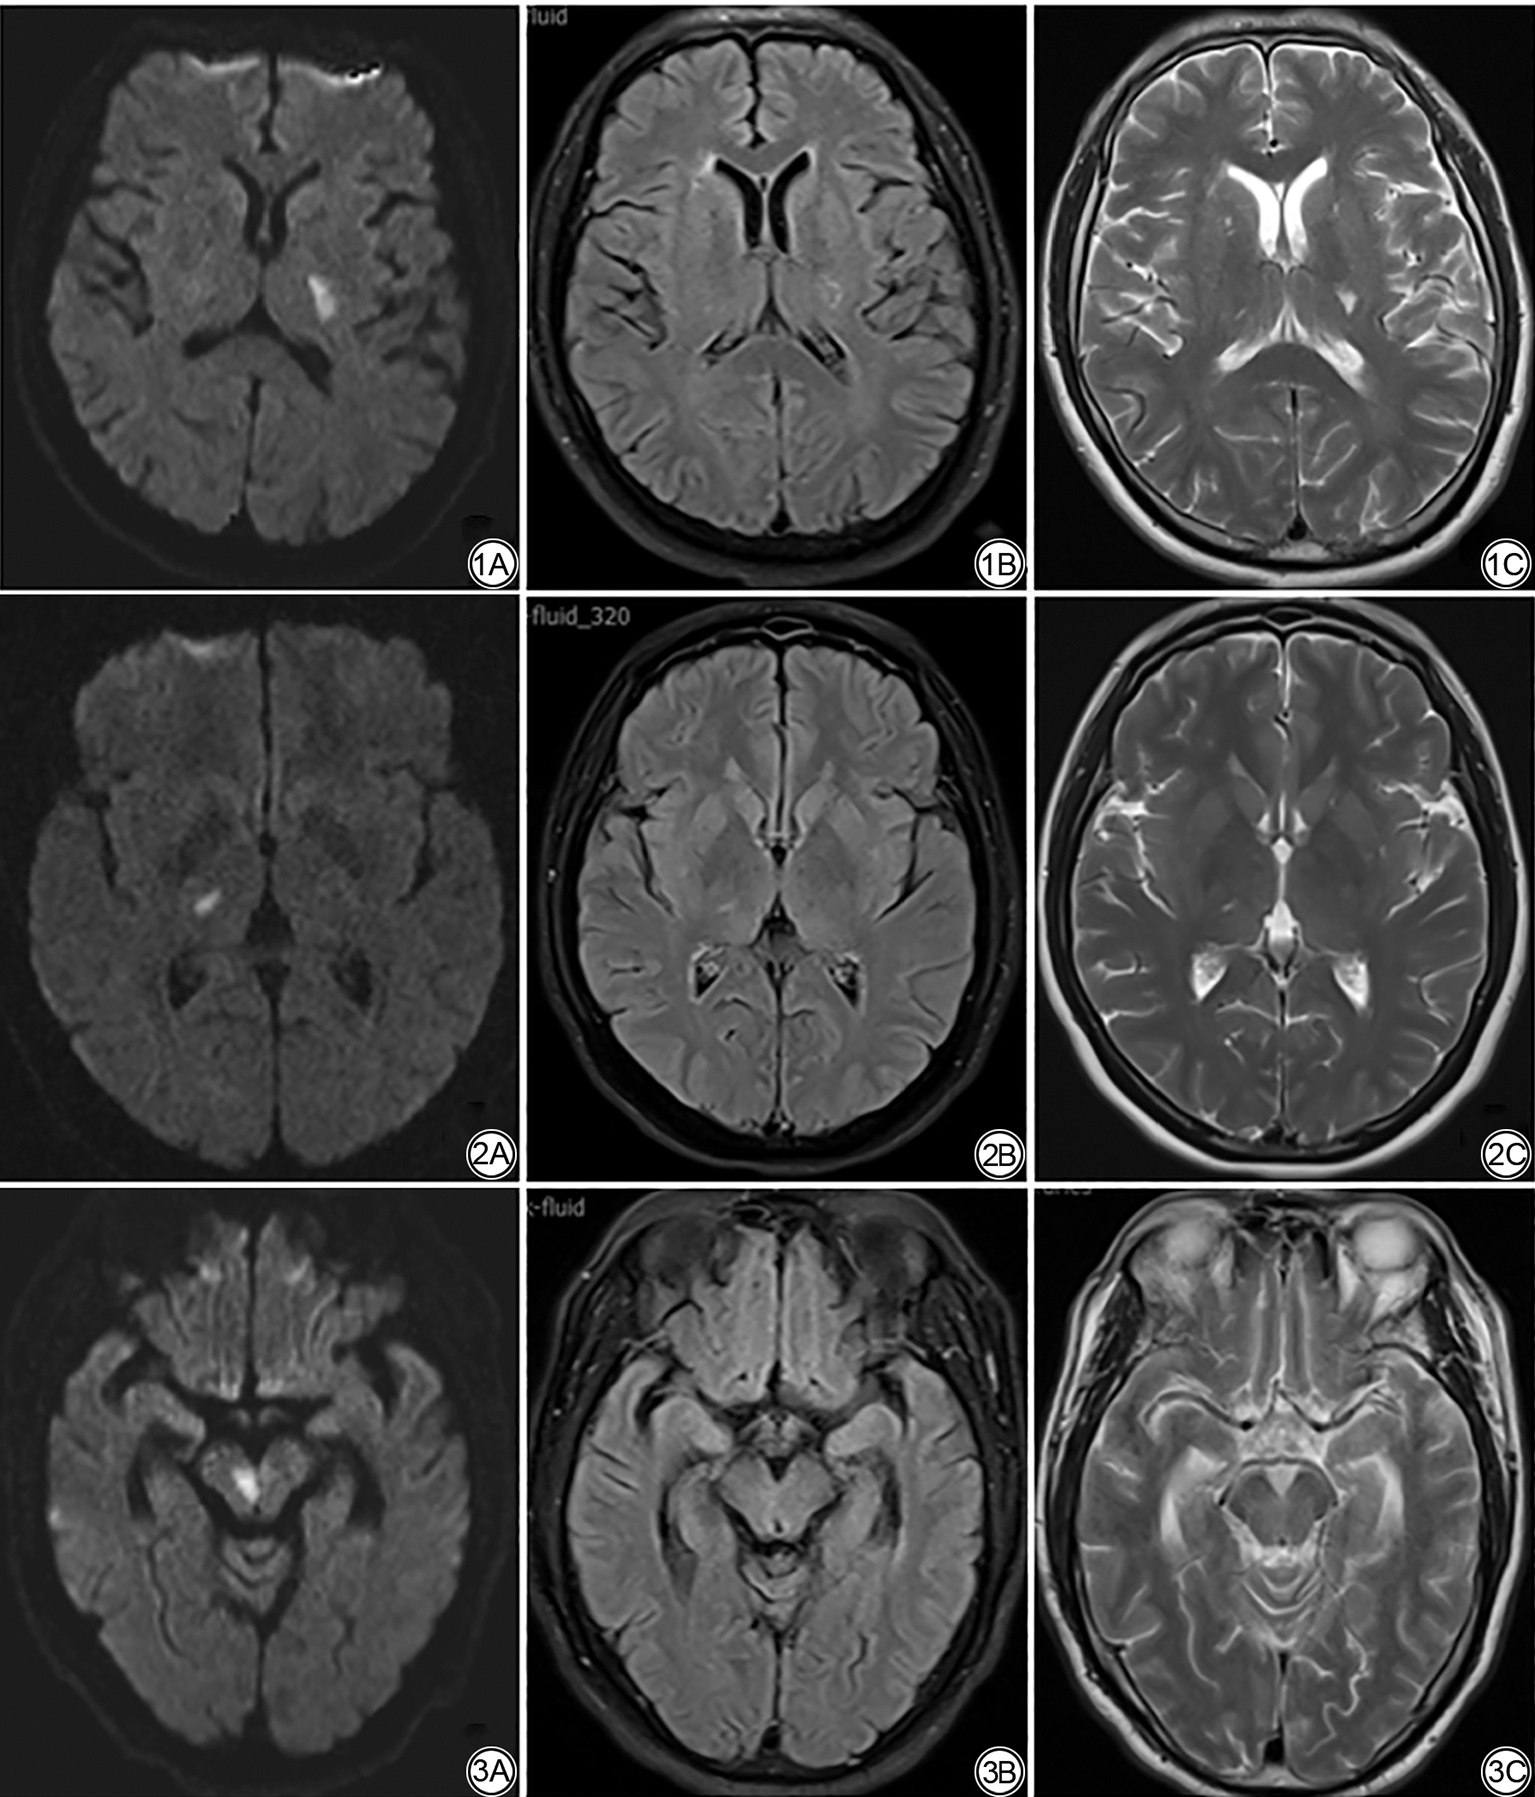

此外,23例RSSI患者入院时及随访期间均加做了SWI检查,中位随访时间为7.50(3.90,12.80)个月。其中12例患者在随访SWI图像上发现HDs现象,呈点状、线状SWI低信号(图4),中位随访时间为8.15(4.30,13.38)个月,其余11例未观察到明显HDs,中位随访时间为6.90(3.30,12.80)个月,HDs阳性组与阴性组间随访时间差异无统计学意义(P=1.000)。12例HDs患者中,8例演变为腔隙灶,4例演变为WMH。

图4  女,59 岁,近期皮质下小梗死灶中出现HDs。4A:头颅DWI 示右侧丘脑梗死灶;4B~4C:随访1.3 个月后,SWI(4B)示病灶内线状低信号(箭),FLAIR(4C)示病灶内部分腔隙化。HDs:含铁血黄素沉积;DWI:弥散加权成像;SWI:磁敏感加权成像;FLAIR:液体衰减反转恢复。

Fig. 4  Female, 59 years old, recent small subcortical infarct lesions with hemosiderin deposits. 4A: DWI of the head image shows infarct in the right thalamus; 4B-4C: After 1.3 months of follow-up, SWI (4B) shows the linear dark signal in the lesion (arrow), FLAIR (4C) shows partial cavitation within the lesion. HDs: hemosiderin deposits; DWI: diffusion-weighted imaging; SWI: susceptibility weighted imaging; FLAIR: fluid attenuated inversion recovery.

3.2 RSSI随访SWI序列上HDs现象

有研究表明HDs与慢性微出血或血管渗漏导致的铁沉积有关,这种沉积可能反映慢性血管损伤,或与血脑屏障破坏后红细胞外渗相关[26, 27, 28]。本研究中23例患者入院及随访期间均加做了SWI检查,HDs发生率为52.2%(12/23)提示其并非少数现象。这一结果与两项前瞻性研究结果接近,XU等[29]报道108例RSSI患者中,55%的患者在卒中发作后3个月内在SWI上出现HDs,76.9%的患者在卒中发作后12个月内在SWI上出现HDs;JIANG等[30]发现在随访约12个月后,将近一半(45/101)RSSI患者在梗死灶内出现HDs。这些研究均表明,HDs在RSSI中较为常见,且与较长的随访时间、较大的病灶体积相关[29, 30]。在本研究的12例HDs患者中,8例演变为腔隙灶,4例演变为WMH,提示HDs与腔隙化结局相关,间接表明HDs与梗死灶直径相关,然而,由于本研究仅部分患者接受了SWI检查,仅初步增进了对RSSI长期演变中HDs现象的理解,未来研究需通过标准化影像检查和延长随访时间,进一步探讨HDs在RSSI演变中的意义。